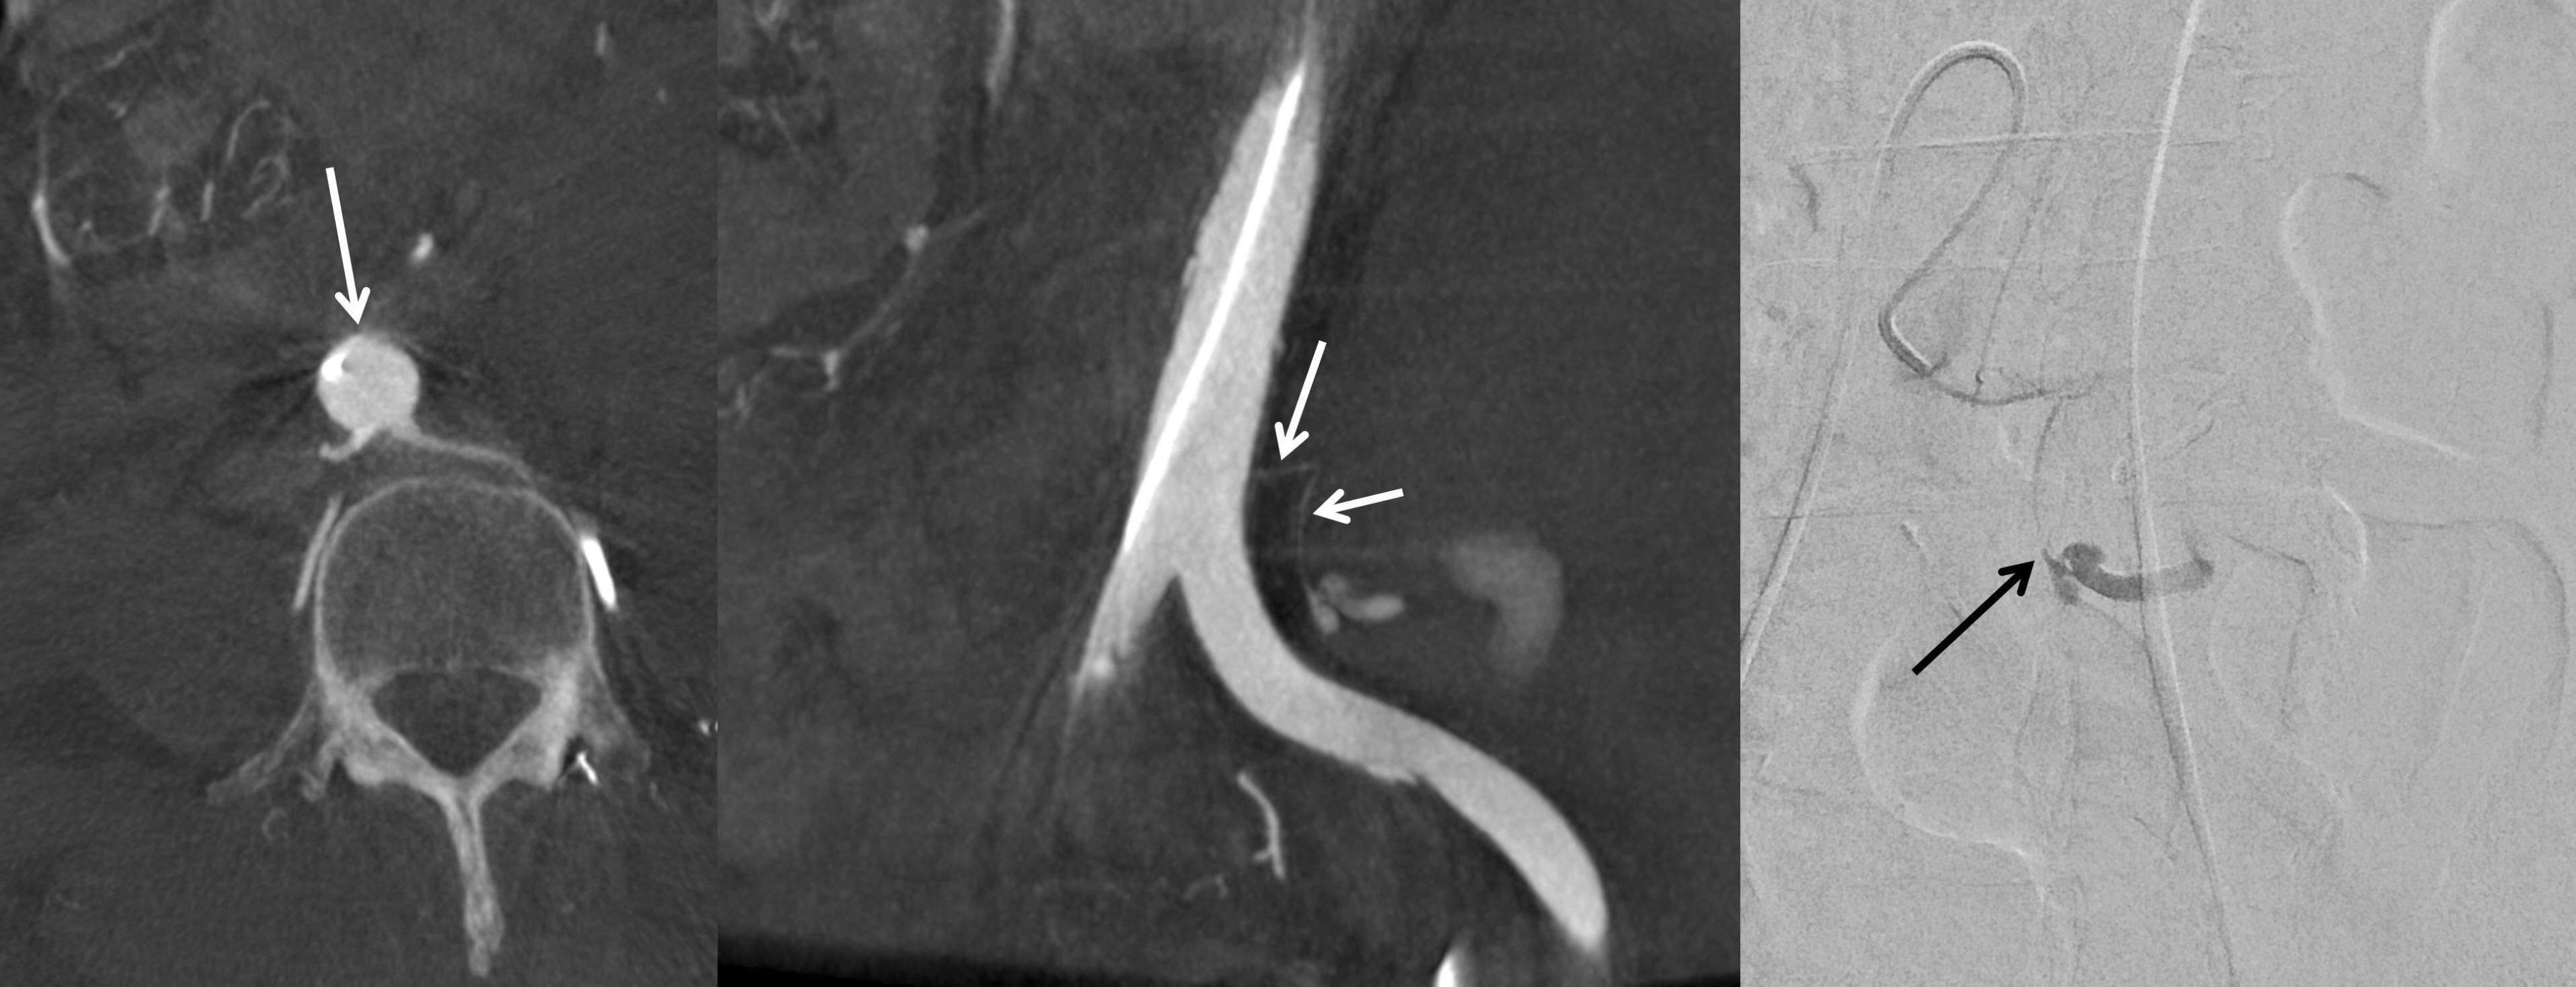

The upper (abdominal) segment of the ureter is primarily supplied by fine ureteric branches originating from the main renal artery. Less commonly, arterial supply may also arise from the abdominal aorta or the gonadal arteries. These vessels approach the ureter medially and bifurcate into ascending and descending branches, forming a longitudinal anastomosis along the ureteral wall [

5] (

Fig. 4). Anatomically, the ureteric artery typically originates laterally from the abdominal aorta. However, in the present case, it appeared to originate anteriorly due to displacement caused by a surrounding hematoma. On follow-up computed tomography, after resolution of the hematoma, the artery was again visualized as originating laterally. This case underscores that an exclusive assumption of a lateral origin from the abdominal aorta may impede the precise identification of the ureteric artery in certain clinical contexts.

Fig. 4.In this schematic drawing of the segmental arterial supply to the ureteric artery, the supplying arteries are depicted as thick black lines: from top to bottom, the renal artery branch, gonadal artery branch, aortic branch, and multiple branches of the internal iliac artery.